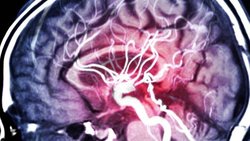

۷ نشانه وقتی کرونا به مغز میزند!

شاید کووید-۱۹ را به عنوان یک بیماری تنفسی در نظر بگیرید که البته درست است، زیرا کروناویروس جدید به ریههای انسان حمله میکند. به گزارش آوای نشاط، به نقل از «ایت دیس» نوشت: دانشمندان، پزشکان و بیماران در حال کشف این مساله هستند که کووید-۱۹ میتواند مغز را نیز آلوده کند و به بروز علائم عصبی مشکلساز در افراد در هر سنی منجر شود.

اگر دشواری در تکلم و درک، فلج یا بیحسی در صورت، دست یا پا، یا بروز مشکلات ناگهانی در دید خود را تجربه میکنید باید کمک پزشکی فوری دریافت کنید. مطالعات نشان دادهاند که در نتیجه افزایش لختهشدن خون، سکتههای مغزی با کووید-۱۹ پیوند خوردهاند و حتی افراد جوان بدون عوامل خطر قبلی برای سکته مغزی نیز وجود لخته خون در سرخرگهای مغز را تجربه کردهاند. این گاهی اوقات بلافاصله و گاهی اوقات پس از ۱۰ روز از ابتلا به عفونت رخ داده است.

اگر تغییر در عملکرد فکری، احساسی، روانی و شخصیتی خود را تجربه می کنید که به طور معمول با تغییرات رفتاری همراه است، ممکن است به انسفالوپاتی مبتلا شده باشید. انسفالوپاتی اصطلاحی در برگیرنده شرایطی است که بر مغز تاثیر میگذارد. به عنوان مثال، یک بیمار مبتلا به کووید-۱۹ دچار سردرگمی شده و از سردرد شکایت داشت. وی تنها میتوانست موارد معدودی مانند نام خود را به پزشکان بگوید و با گذشت زمان میزان پاسخگویی وی هرچه بیشتر کمتر میشد. اسکنهای مغزی تورم غیرعادی و التهاب در چند بخش مغز وی و همچنین مرگ سلولها در بخشهایی کوچکتر را نشان دادند.